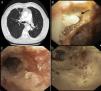

A 71-year-old man with a history of lung adenocarcinoma diagnosed and treated in 2006 with concomitant chemo- and radiotherapy, presented in February 2015 with recurrent respiratory infections. Chest and abdomen computed tomography (Fig. 1A) showed stenosis of the left main bronchus. Flexible bronchoscopy revealed: (a) left lower paratracheal ulcerative lesion covered with mucopurulent secretion (Fig. 1B) and (b) pseudomembranous mucosa in the distal third of the trachea and left main bronchus (Fig. 1C). The left main bronchus was successfully dilated with a balloon catheter (CRE™ Pulmonary; Boston Scientific) (Fig. 1D). Tracheobronchial aspiration was performed in the left main bronchus and endobronchial biopsies were obtained from the ulcerative lesions. The biopsy revealed bifurcated hyphae at 45° angles, with positive Grocott staining, confirming the diagnosis of Aspergillus fumigatus. Culture of the tracheobronchial aspirate was positive for Aspergillus fumigatus.

(A) Loss of volume in the left hemithorax with stenosis of the left main bronchus and bronchiectasis in the apical segment of the right upper lobe. (B) Left lower paratracheal ulcerative lesion covered with mucopurulent secretion (arrow). (C) Pseudomembranous mucosa in the distal third of the trachea and left main bronchus. (D) Balloon catheter dilation of stenosis in left main bronchus.